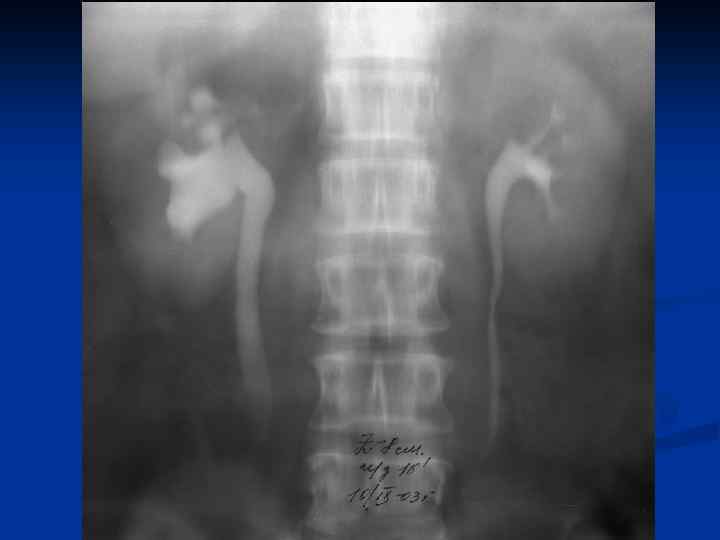

n n n Провести рентгеновское исследование грудной клетки, а если есть показания, то и других органов; Определить туберкулиновую чувствительность; Назначить и провести гистеросальпингографию с 60% раствором водорастворимого верографина, при этом возможно: n n n Определить состояние маточных труб (тонкие, ригидные, запаянные ампулярные отделы, деформация в виде четок, курительных трубок); Выявить форму полости матки, ее размеры, наличие или отсутствие сокращений; Диагностировать наличие / отсутствие рефлюкса контрастного вещества из труб.